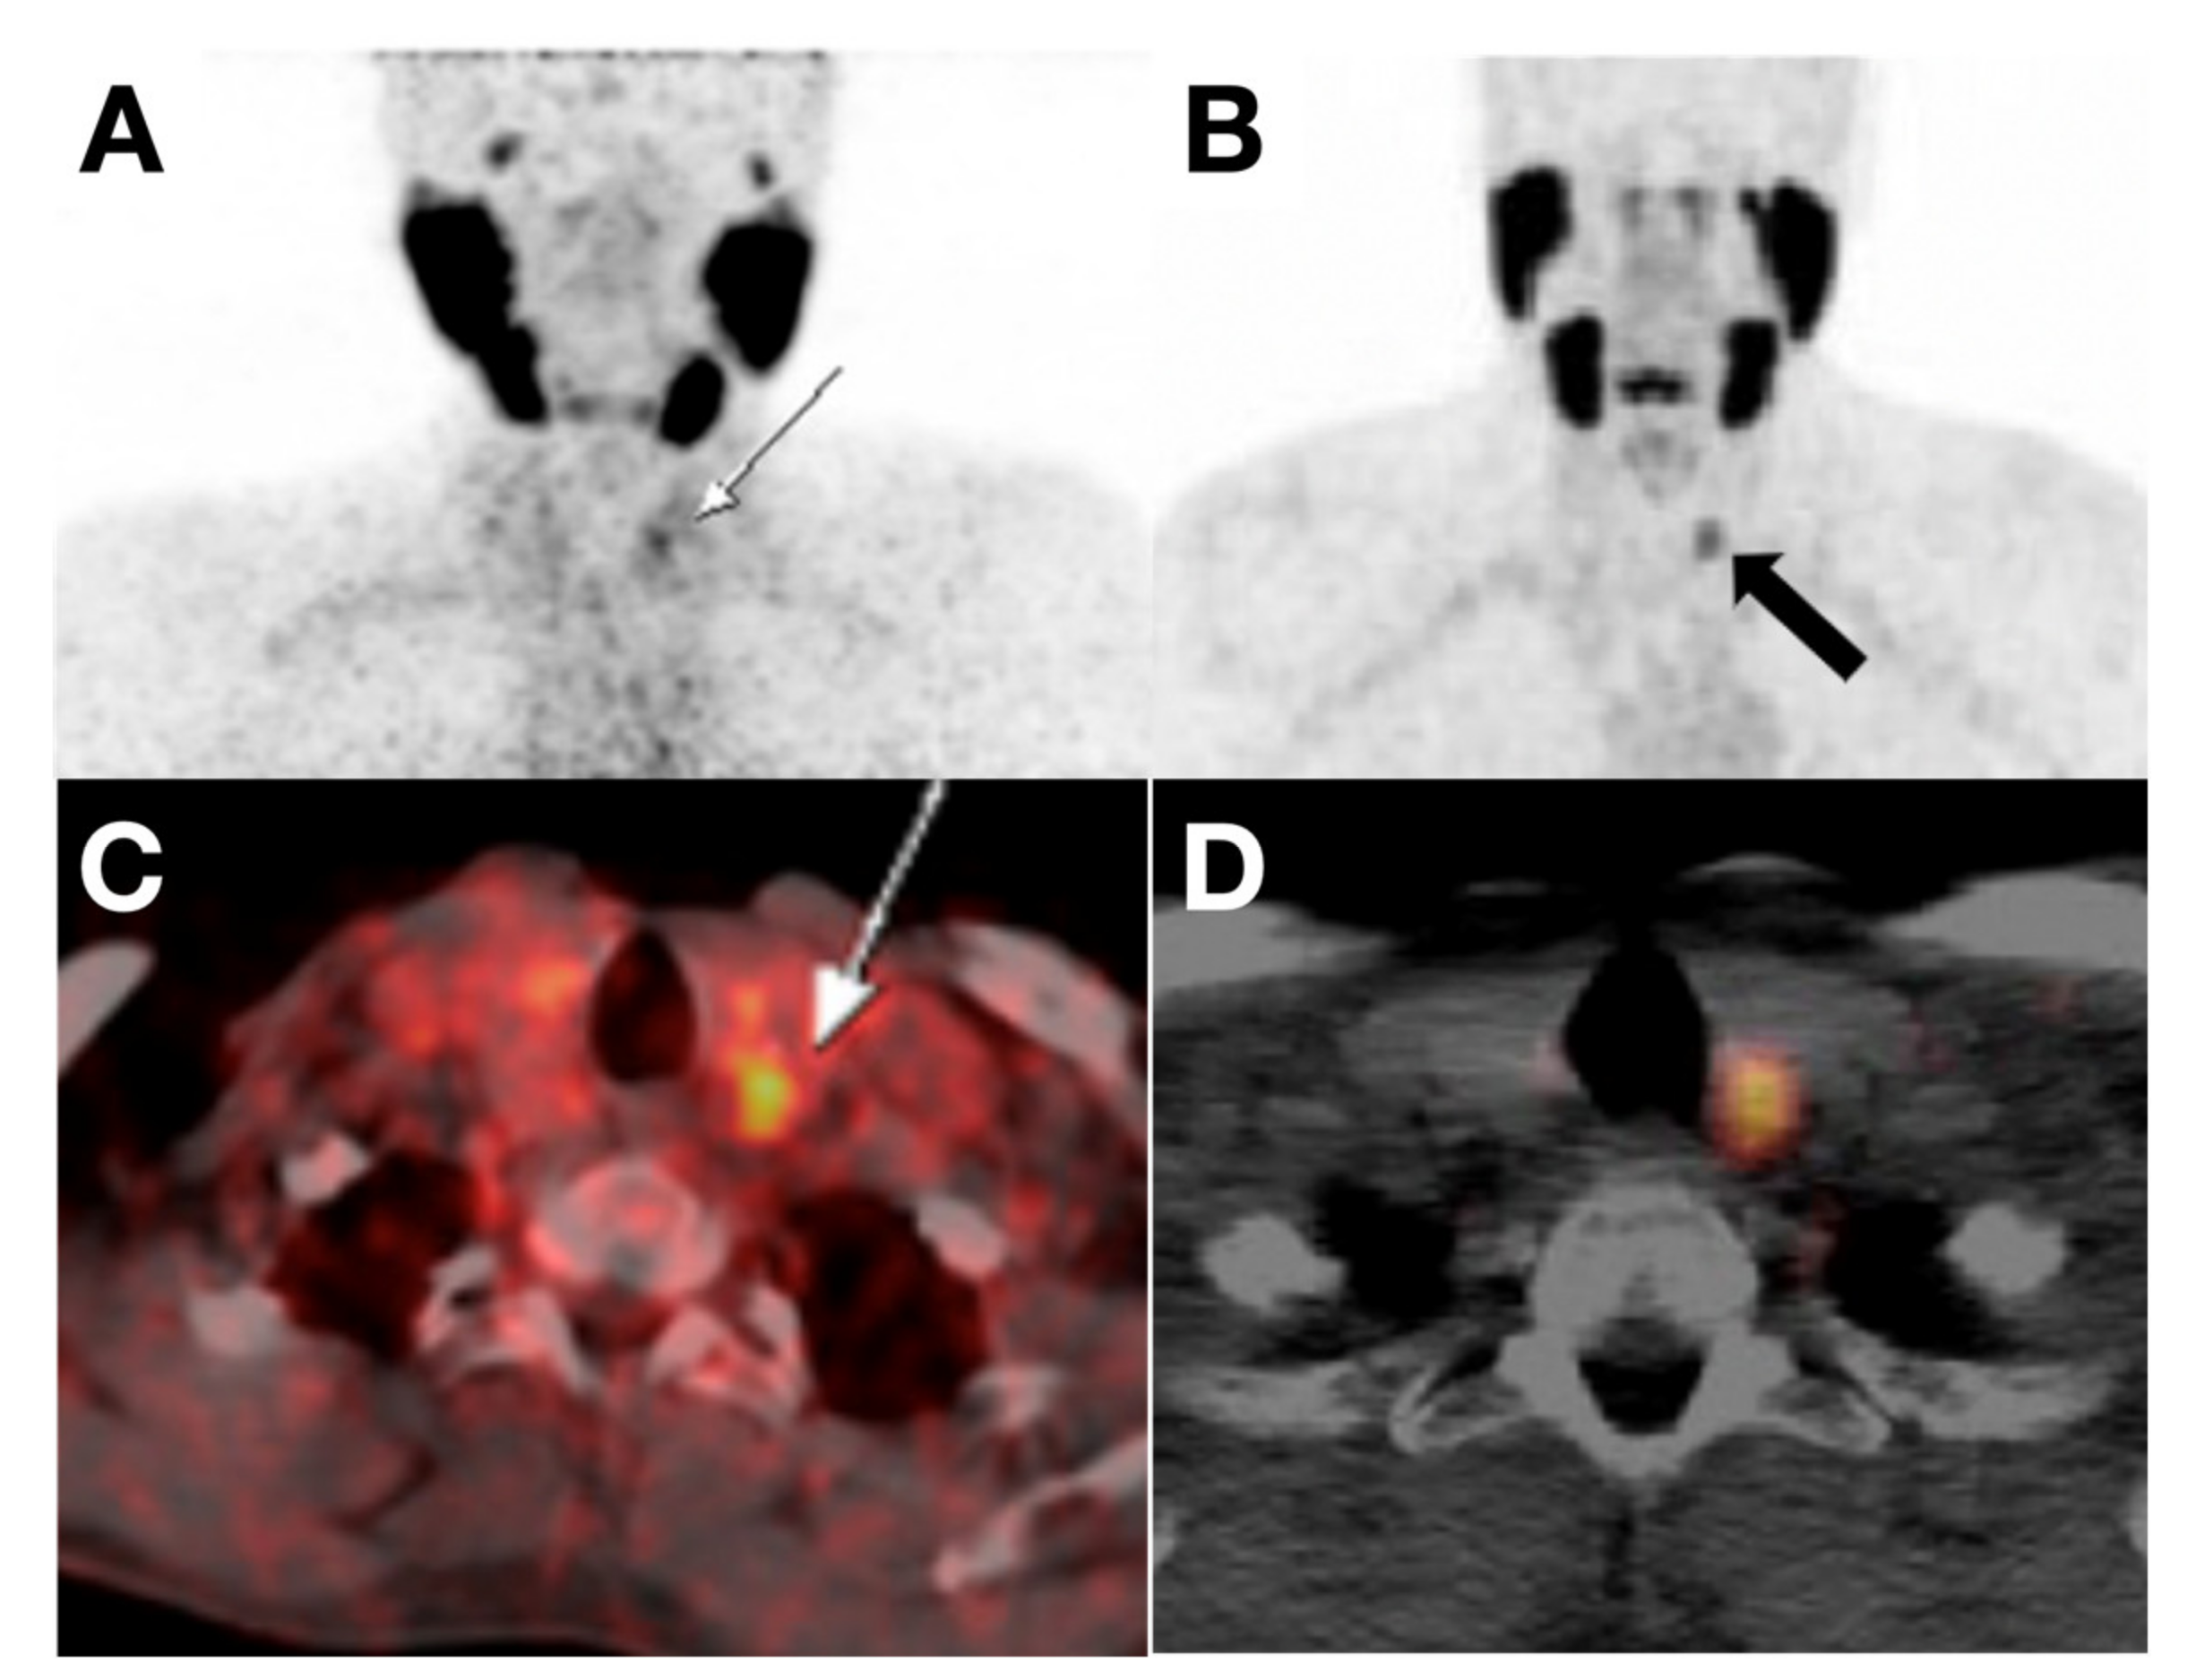

- Parihar, A.S.; Mittal, B.R.; Kumar, R.; Shukla, J.; Bhattacharya, A. 68Ga-DOTA-RGD2 Positron Emission Tomography/Computed Tomography in Radioiodine Refractory Thyroid Cancer: Prospective Comparison of Diagnostic Accuracy with 18F-FDG Positron Emission Tomography/Computed Tomography and Evaluation Toward Potential Theranostics. Thyroid Off. J. Am. Thyroid Assoc. 2020, 30, 557–567. [Google Scholar] [CrossRef]

- Parihar, A.S.; Sood, A.; Kumar, R.; Bhusari, P.; Shukla, J.; Mittal, B.R. Novel Use of 177Lu-DOTA-RGD2 in Treatment of 68Ga-DOTA-RGD2-Avid Lesions in Papillary Thyroid Cancer with TENIS. Eur. J. Nucl. Med. Mol. Imaging 2018, 45, 1836–1837. [Google Scholar] [CrossRef]